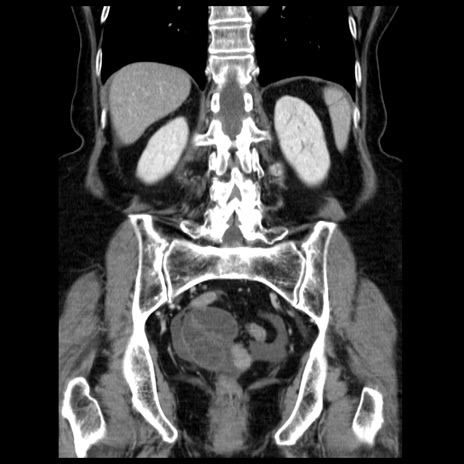

横断像